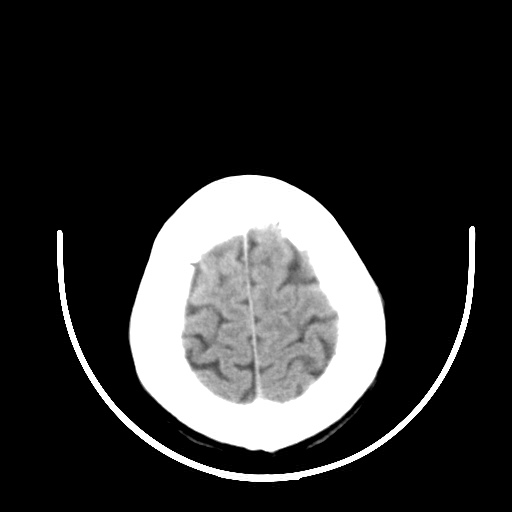

标题: CT16579:女 65岁间断性抽搐. [打印本页]

标题: CT16579:女 65岁间断性抽搐.

老年脑改变

脑软化灶!

考虑右颞叶脑软化灶